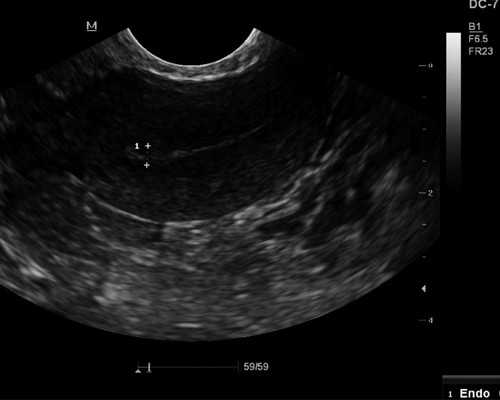

1、女性可以从月经周期的第5天或第6天到医院进行基本卵泡数量检查。如有必要,也可以进行B超声卵泡监测,每2天到医院进行一次超声监测,通过B超声检查可以准确反映基本卵泡发育的大小和基本卵泡的质量。当卵泡直径达到15mm时,应每天监测一次。当卵泡发育到18毫米以上时,此时卵泡已发育成成熟卵泡,可每天监测两次,直至排卵。2、一般来说,女性卵巢中的卵泡直径越大,卵泡监测的次数就越频繁。女性去医院做卵泡监测的方法有很多,常用的是B超声监测,检查基本卵泡的时间通常在月经的第五天开始,然后每隔一天监测一次,直到排卵。什么时候检查卵泡合适?

1、优势卵泡破裂后,可能引起少量盆腔积液,引起少量腹痛。建议观察3天左右吸收,不影响身体健康。2、如果在监测过程中发现有优势卵泡,此时可以同房,有助于提高受孕率。3、如何检查卵泡发育情况,卵泡发育可以进行卵泡监测。4、根据监测情况,卵泡可以每隔一天或每隔一天监测一次,直到有优势的卵泡出现,说明卵泡发育良好。5、从月经第一天到第11天,什么时候检查卵泡?6、如果做卵泡监测,从月经第10天开始检查。7、卵泡大小约0.5-0.6cm,正常情况下,卵泡每天会以1.5-2mm的速度*长。8、目前,监测卵泡的方法主要是通过*彩色多普勒超声进行。*彩色多普勒超声的优点是不需要喝水来抑制尿液。如果在监测过程中没有发现优势卵泡,可以每隔1到2天到医院进行监测。9、随着时间的推移,到月经的第16天,卵泡就会达到2.0cm,这个时候会破裂,排出卵子,所以这个时候检查比较好。